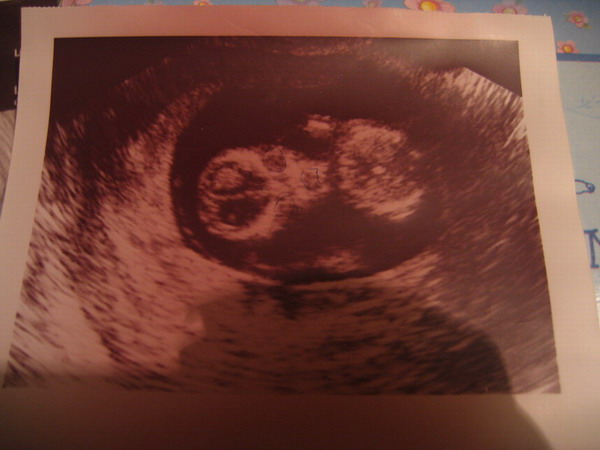

Végre feltöltöttem a fényképező aksiját, úgyhogy felrakom Kisborsó múlt hétfői (12+4) UH képét :D (amit tollvonásokat láttok a képen, az akkor történt amikor a doki magyarázta, hogy mit is látunk pontosan a képen, és nyitva maradt a tolla...:roll: )

Kép